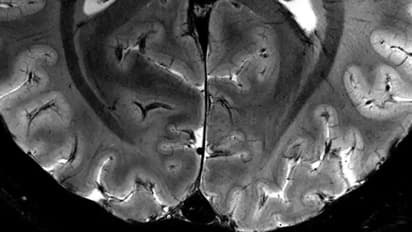

The scanner's magnetic field, measuring a staggering 11.7 teslas, is named after inventor Nikola Tesla, marking a significant leap in scanning capability. This level of power enables the machine to produce images with tenfold precision compared to the MRIs typically found in hospitals, which typically operate at three teslas or less.

Vignaud compared images captured by the formidable scanner, dubbed Iseult, with those obtained from a standard MRI, highlighting the remarkable difference in clarity and detail.

"With this machine, we can see the tiny vessels which feed the cerebral cortex, or details of the cerebellum which were almost invisible until now," he added.